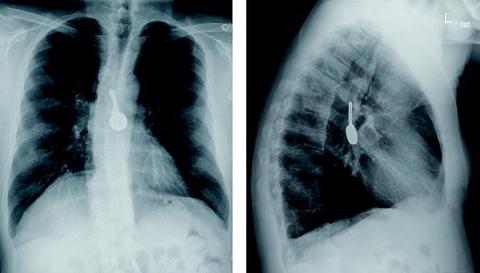

En 56-årig alkoholiker blev indlagt akut på grund af mistanke om hæmatemese. Dette blev dog afkræftet, idet der var tale om tidligere indtaget kirsebærvin. På grund af infektionstegn blev der udført røntgenoptagelse af thorax i to planer. Billederne viste en nøgle beliggende i øsofagus. Patienten havde ingen erindring om, hvornår eller hvordan nøglen var indtaget. Med rigidt øsofagoskop fjernedes nøglen, der lå 37 cm fra tandrækken. En efterfølgende fleksibel øsofagoskopi i samme anæstesi viste overraskende også en tikrone, der lå på nøjagtigt samme sted som nøglen. Denne blev ligeledes fjernet. Øsofagusslimhinden var hyperæmisk i det område, hvor fremmedlegemerne havde ligget, men der var ingen tegn til perforation. På en postoperativ røntgenoptagelse af thorax sås der ingen fremmedlegemer. Patienten blev behandlet med antibiotika og udskrevet i velbefindende kort tid efter.

Ovenstående sygehistorie illustrerer vigtigheden af kontroløsofagoskopi distalt for området, hvor et fremmedlegeme er blevet fjernet. Røntgenoptagelse af thorax med fremstilling af fremmedlegemer bør være i to planer, så tilstedeværelsen af flere fremmedlegemer ikke overses [1, 2]. Selv med røntgenoptagelse i to planer kan flere fremmedlegemer dog - i sjældne tilfælde som vores - fejltolkes som et enkelt fremmedlegeme [3].